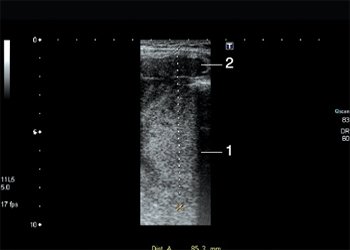

Рис. 1. Эхограммы костного дефекта, экстра- и интракраниального компонентов опухоли. Линейный датчик (7,5-15 МГц). Двухмерное исследование в серошкальном режиме. Продольное сечение.

При исследовании, выполненном на современном сканере с использованием линейного мультичастотного датчика (7,5-15 МГц) и режимов серой шкалы, тканевой гармоники, цветового и энергетического допплеровского картирования (ЦДК, ЭД), было установлено следующее: в правой височной области подкожно, в структуре апоневротического слоя визуализируется гипоэхогенное образование размером 5,2x4,5x2,6 см, неправильной, ближе к овальной, формы, с неровными, локально нечеткими, «фестончатыми» контурами, неоднородное, с единичными гиперэхогенными включениями до 0,1 см (по типу микрокальцинатов), без акустической тени, с единичными анэхогенными включениями до 0,7 см, без четко выраженной капсулы. В режимах ЦДК, ЭД в структурах опухолевого фокуса отмечено локальное усиление кровотока. Образование незначительно сжимаемое, безболезненное при компрессии. Задними отделами образование примыкает к костям свода черепа, где определяются прерывистость надкостницы, дефект костных структур черепа на протяжении 1,7-1,9 см. Края дефектов нечеткие, неровные, локально утолщены до 0,3 см. С другой (внутренней) стороны черепа к костному дефекту примыкает вторая часть образования неправильной формы размером примерно 2,3x2,5x4,2 см (в отделах, доступных для визуализации). По эхогенности, эхоструктуре, васкуляризации внутричерепная часть опухолевого фокуса полностью аналогична описанному выше в мягких тканях височной области, соединяется с ним перемычкой шириной до 1,9 см. Лимфатические узлы шеи (яремные группы), подчелюстные, подбородочные не увеличены, без признаков опухолевого поражения (рис. 1-5).

Рис. 2. Эхограмма интракраниального компонента опухоли через структуру кости. Линейный датчик (7,5-15 МГц). Двухмерное исследование в серошкальном режиме. Продольное сечение.